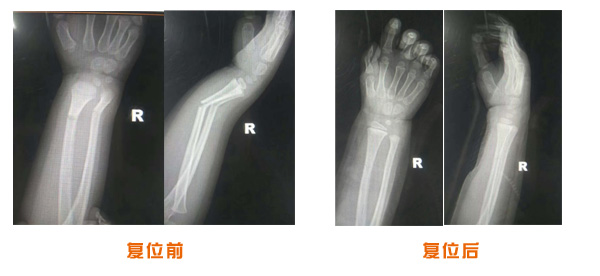

尺橈骨骨折治療前后